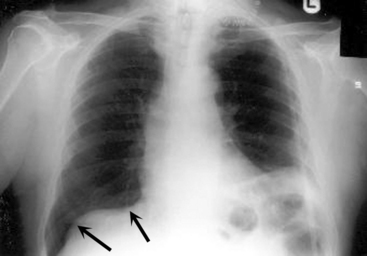

image

Fig. 10-17 Right upper and middle lobe pneumonia. There is a dense opacity of the right upper lobe consistent with pneumonia. There is also hazy opacification along the right heart border. This opacification is caused by the fluid density of right middle lobe pneumonia obliterating the silhouette of the heart. This silhouette sign enables localization of the pneumonia to the right middle lobe.